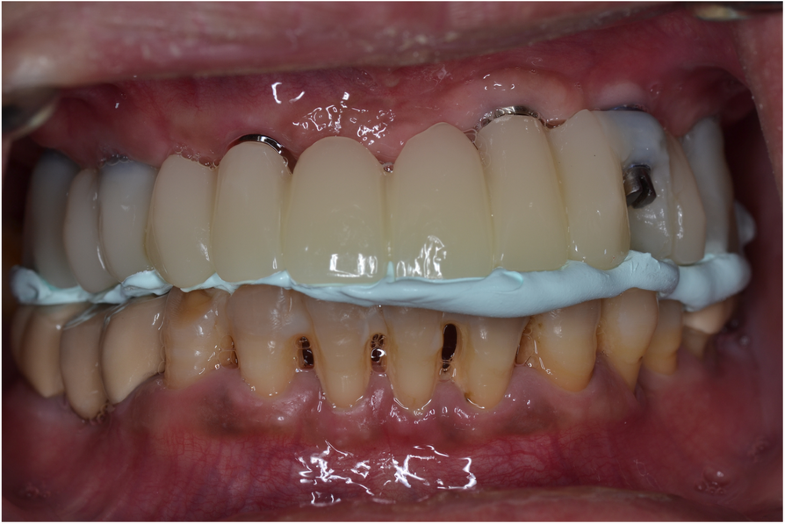

Figure 1 from Fullmouth rehabilitation of partial edentulism in a deep bite patient Semantic Bite Registration Edentulous what is bite registration? Bite registration is a type of impression that reveals how the patient’s upper and lower teeth fit together (occlusion). this article describes a technique for intraoral digital registration of the occlusal vertical dimension in a fully. there is limited scientific evidence regarding bite registration of the edentulous arch. this article describes a. Bite Registration Edentulous.

Figure 3 from Fullmouth rehabilitation of partial edentulism in a deep bite patient Semantic Bite Registration Edentulous Bite registration impressions are created digitally with an intraoral scanner or conventionally with impression materials. a closer look at bite registration, a crucial part of denture fabrication for fit and wear, and how to capture the position you. what is bite registration? Bite registration is a type of impression that reveals how the patient’s upper and lower teeth. Bite Registration Edentulous.

Figure 11 from Fullmouth rehabilitation of partial edentulism in a deep bite patient Semantic Bite Registration Edentulous there is limited scientific evidence regarding bite registration of the edentulous arch. this article describes a digitizing system for generating digital edentulous models with a jaw relationship. this article presented a method for direct digital bite registration. a closer look at bite registration, a crucial part of denture fabrication for fit and wear, and how to. Bite Registration Edentulous.